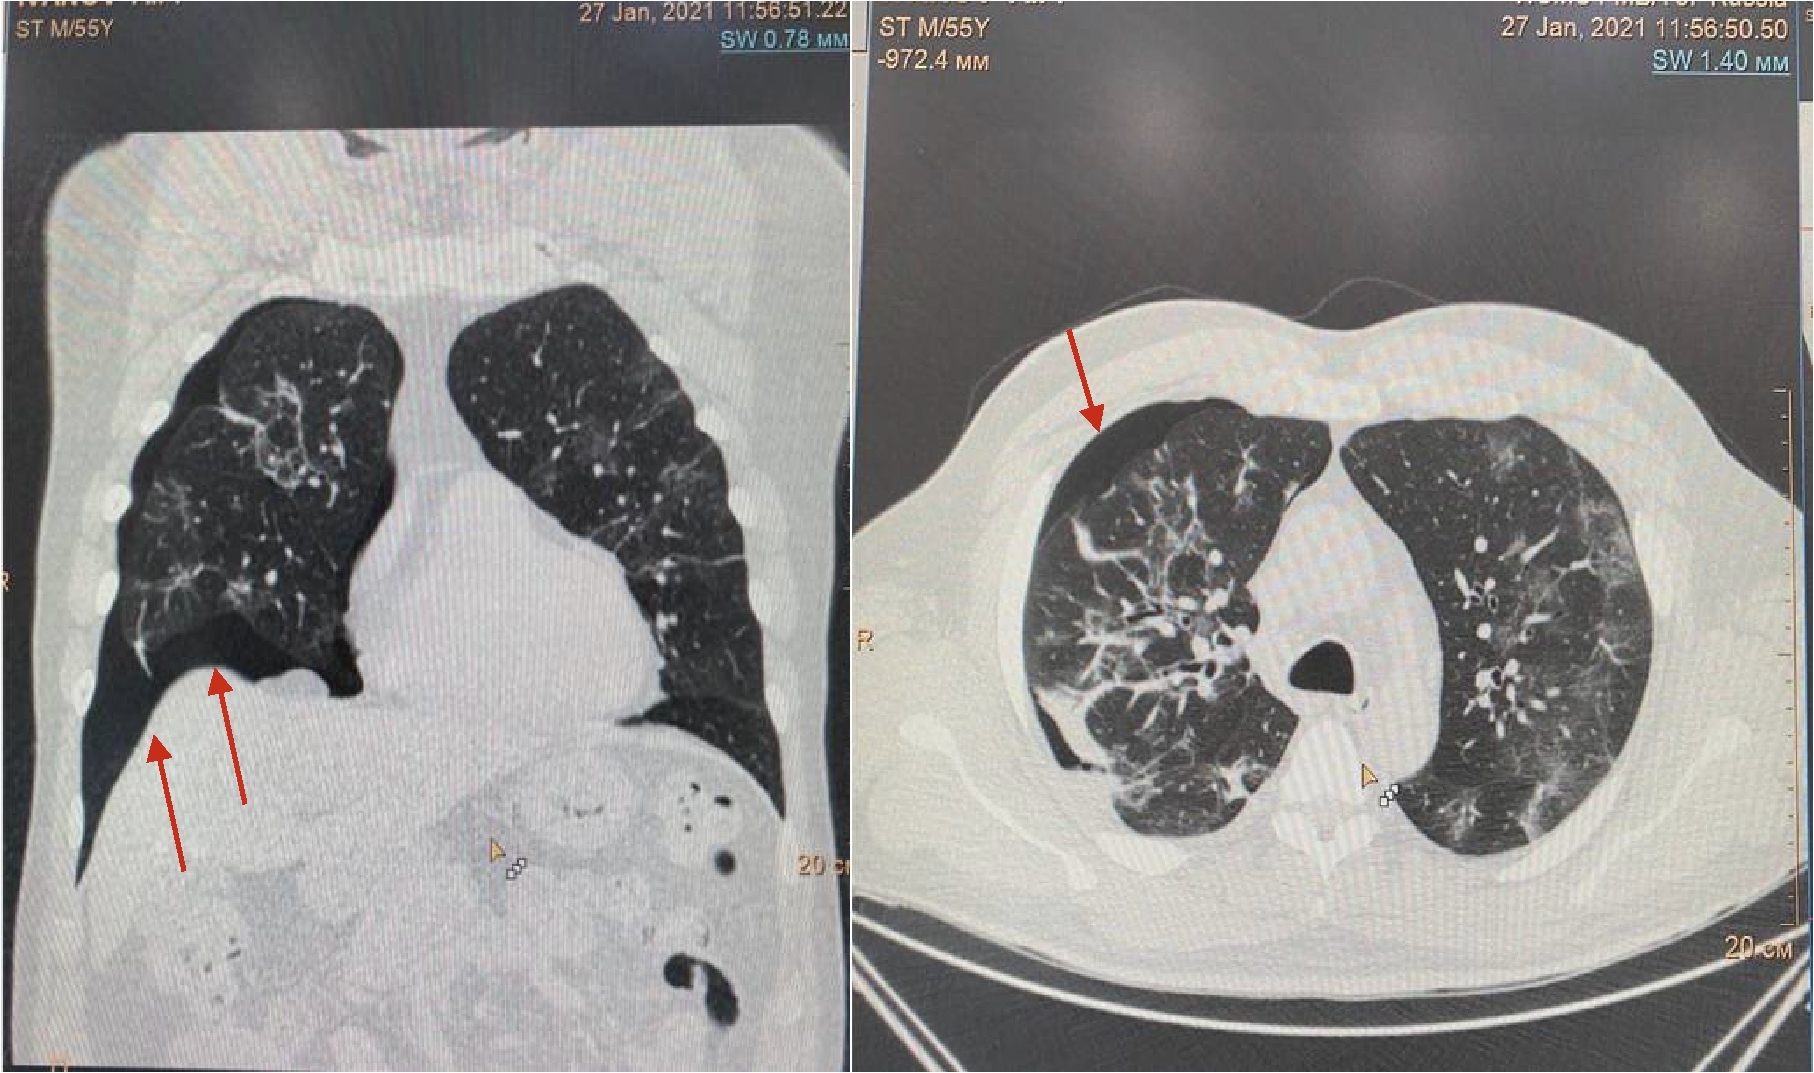

Рисунок 2. МСКТ органов грудной клетки – признаки двусторонней полисегментарной интерстициальной пневмонии (объем поражения 40%, КТ-2)

На 4-е сутки госпитализации выявлено ухудшение клинического статуса (снижение SpO2 до 93%, температура тела более 38 0С), отрицательная динамика по МСКТ (объем поражения 28%, КТ-2, в связи с чем к лечению добавлен олокизумаб однократно, без отчетливого клинического эффекта. На 7-е сутки госпитализации МСКТ выявила дальнейшее прогрессирование поражения легких (объем поражения 40%, КТ-2 (рис.2) на фоне сохранения умеренно выраженного кашля (со скудной мокротой), нарастания дыхательной недостаточности (SpO2 85-88% без инсуффляции кислорода). Больной переведен в отделение анестезиологии и реанимации, где находился в течение 3 суток, лечение включало преднизолон 480 мг/сут (начальная доза), противокашлевый препарат центрального действия (бутамират), проведен плазмоферез (аппарат Fenwal; инфузия плазмы - 2440 мл, эксфузия плазмы - 1430 мл) с введением антиковидной плазмы (270 мл).